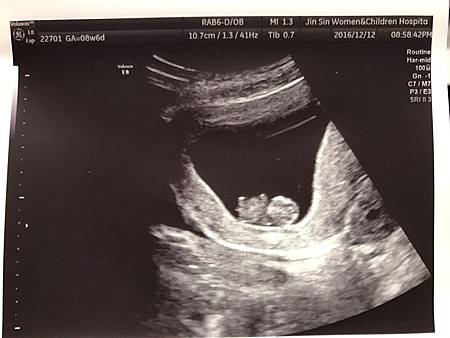

詠馨跟璟馨醫院的設備不太一樣,璟馨設備比較新一代,所以光是寶寶超音波照片,清晰度就真的有差。

N.T.九週和三十四週左右的超音波照,這不是高層次超音波檢查拍的唷,是不是超級清晰!!!

想當初一看到這樣的超音波照片,完全融化我的心,常常看到都會鼻子酸酸(感動說不出口,哈哈)